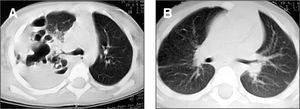

Varón de 2 años, que ingresó por fiebre de 41 °C, tos, diarrea y rechazo alimentario. Presentaba un regular estado general, 36 resp./ min, 120 lat./min, temperatura 39,8 °C, palidez y sudoración. A la auscultación existía soplo tubárico en hemitórax derecho y semiología de derrame pleural en el tercio inferior y zona paraescapular, siendo el resto normal. La analítica reveló 17.300 leucocitos/μl con desviación a la izquierda; sodio, 132 mmol/l; proteína C reactiva, 15,7 mg/dl, y dímero D > 7 μg/ml. La gasometría arterial fracción inspiratoria de oxígeno (FiO2) al 21 % mostró pH, 7,37; PO2, 31,2 torr; PCO2, 39,3 torr; HCO3, 22 mmol/l y saturación del 58 %. En la radiografía de tórax se observó una opacidad en hemitórax derecho, broncograma aéreo en lóbulo medio y lóbulo inferior derecho y condensación alveolar en lóbulo superior derecho con derrame organizado (fig. 1A). Se inició oxigenoterapia, antitérmicos, cefotaxima 200 mg/kg/24 h i.v. y vancomicina 15 mg/kg/6 h i.v. La radiografía del tercer día mostró desplazamiento mediastínico contralateral a expensas de derrame pleural e imágenes areoladas en lóbulo superior derecho, con loculación y organización, y se consultó a la UCI para inserción de tubo de drenaje. El líquido pleural presentaba aspecto purulento; pH, 7,26; 660 leucocitos/μl (95 % polimorfonucleares), glucosa, 2 mg/dl; proteínas, 3,8 g/dl, y LDH 7.090 U/l. Los cultivos, el Ziehl y Löwenstein fueron negativos, así como los hemocultivos, y la prueba de tuberculina. Tras la inserción del tubo torácico, en la radiografía se apreció derrame loculado e imagen cavitada de paredes gruesas, instilándose durante 2 días consecutivos 100.000 U de urocinasa intrapleural. A las 48 h, y habiendo drenado mínimamente, en una ecografía se apreció ausencia del tubo en la cavidad pleural, extrayéndose el mismo. Durante los 6 días siguientes continuó séptico y la radiografía mostró múltiples niveles hidroaéreos por loculaciones pleurales y cavitaciones en lóbulo superior derecho (fig. 1B). En la TC torácica (fig. 2A) se confirmó amplia destrucción con necrosis parenquimatosa en lóbulo superior derecho y colapso del lóbulo inferior derecho con sinequia pleural anterior en el seno del empiema, por lo que se colocó nuevo tubo torácico. El drenaje fue prácticamente nulo en los días siguientes. Una segunda TC torácica reveló que el tubo estaba nuevamente fuera de la cavidad pleural. En este momento (día 13 de ingreso), se consultó con neumología, y se decidió insertar un tercer tubo de drenaje, con control exhaustivo, obteniendo 475 ml de líquido purulento acompañado de burbujeo persistente con la aspiración, traduciendo la presencia de fístula broncopleural. El paciente presentó una mejoría clínica y radiológica espectacular, con reexpansión pulmonar y resolución de las lesiones cavitarias de lóbulo superior derecho. Al mes y medio del alta, la TC mostró desaparición de las cavidades, con tractos fibrosos y refuerzo pleural, y a los 8 meses ausencia de lesiones (fig. 2B).

Figura 2. A)TC torácica que muestra amplia destrucción con necrosis parenquimatosa en lóbulo superior derecho y colapso del lóbulo inferior derecho con sinequia pleural anterior en el seno del empiema y fístula broncopleural.B)TC torácica 8 meses después del inicio del cuadro, en la que se aprecia ausencia completa de lesiones.